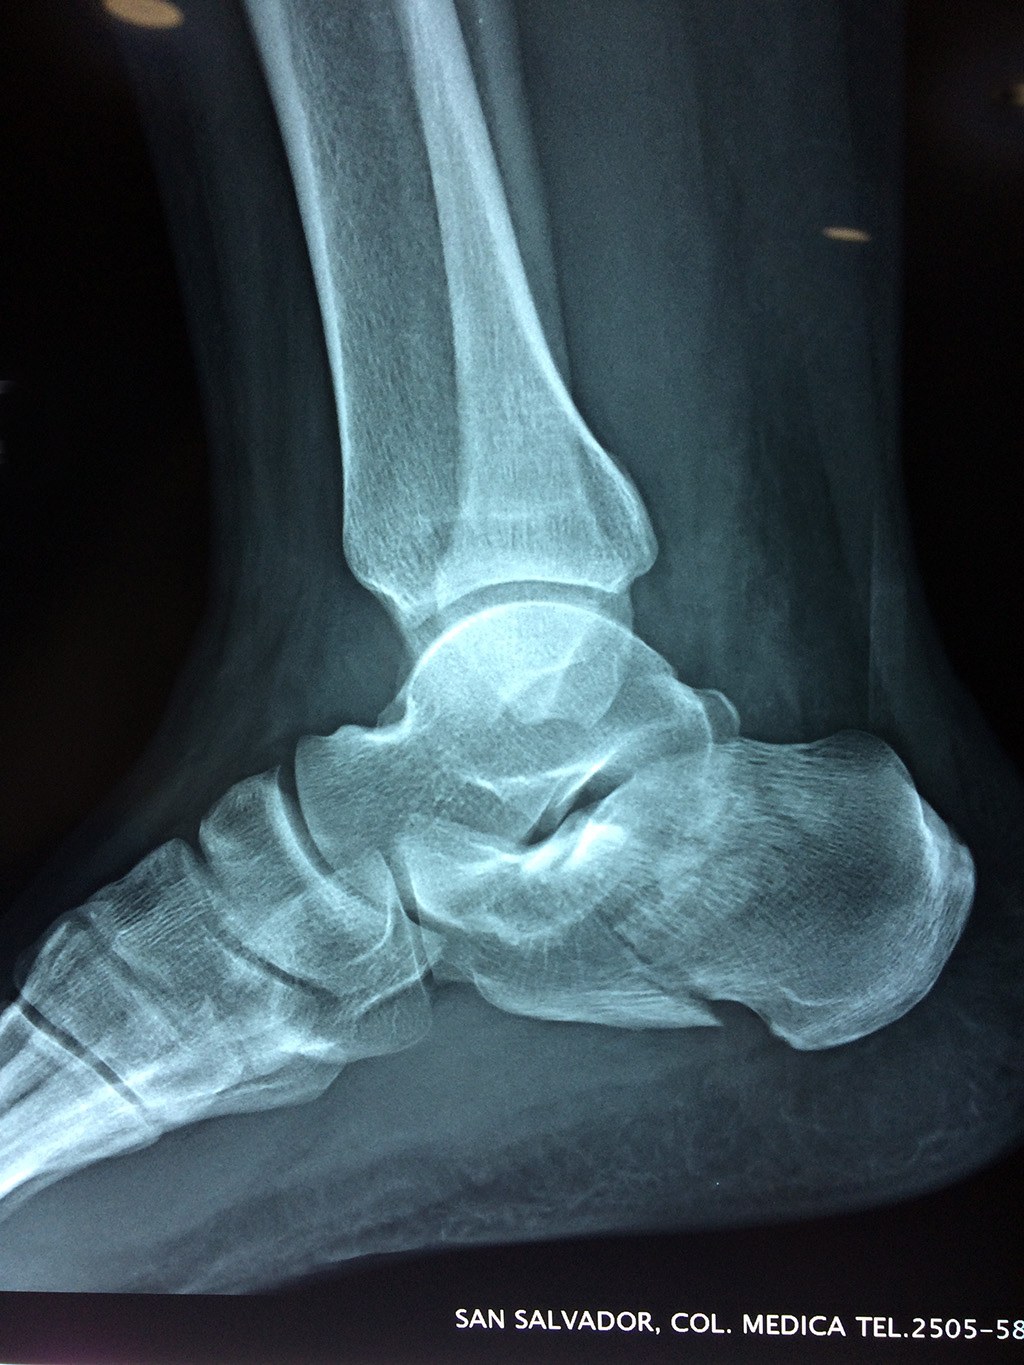

En su cara posterior recibe la inserción del tendón más plantar, implicada en diversas enfermedades como la fascitis o el espolón calcáneo. La posición del calcáneo en relación al astrágalo (articulación subastragalina) y al suelo determinan la posición de retropié en varo, en valgo o neutra.

Los retropiés varos y sobre todo, los retropiés valgos, son responsables de distintas enfermedades del aparato locomotor y contribuyen a que aparezcan alteraciones de la marcha normal fisiológica, con consecuencias clínicas importantes (dolor, sobrecargas, aplanamiento, fatiga muscular, juanetes, etc.) tanto a nivel de pie como a nivel del miembro inferior.

De todo esto se deriva que su posicionamiento espacial es muy importante para contribuir a una marcha correcta y a la salud del resto del conjunto articular del pie.